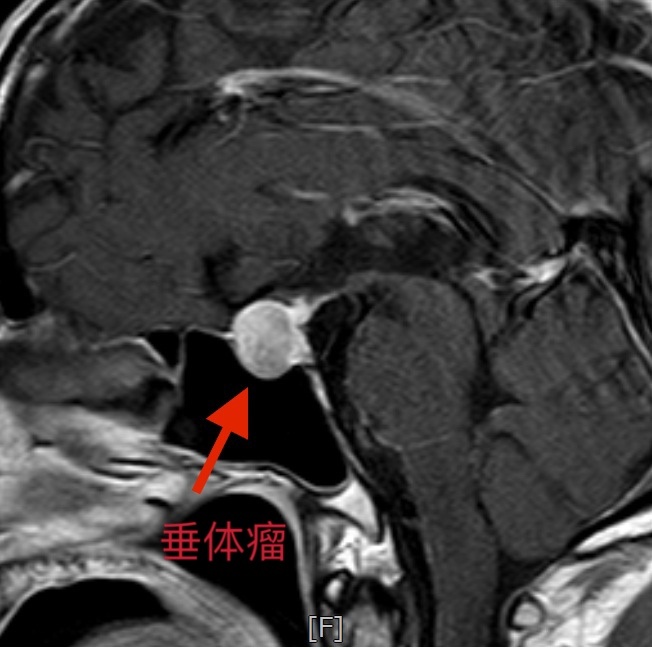

家住崇州的赵大哥最近碰上了烦心事,每天早晨一起来总感觉眼睛蒙上了一层雾,使劲揉两下才勉强觉得好点。“可能是最近工作太忙,手机看多了,没什么大问题“赵大哥误以为眼疾就没放在心上;可日子一天天过去,赵大哥的视力就不见好转,他挂眼科也没有检查出什么异常,最后辗转到成都市第五人民医院神经外科门诊才找到了“元凶”——垂体瘤。

经过一系列住院检查后,赵大哥确诊为无功能性垂体大腺瘤,手术指征明确,于3月25号由刘嘉副主任医师和马栋斌主治医师共同实施了手术。手术过程中,主刀刘嘉医生发现赵大哥的肿瘤包膜很完整,在内镜下,耐心地分离肿瘤包膜和正常垂体的界限,最终完整的切除垂体瘤。手术不到2个小时就结束,出血不到20ml。

神经外科罗霜主任表示:垂体瘤虽然是良性肿瘤,但仍可能因为切除不干净,导致肿瘤再次复发。而赵大哥所做的内镜手术,采用的是目前国内领先的“假包膜”技术,内镜完美剥离出肿瘤的包膜,实现了垂体瘤的全切除,并将周围的重要神经、血管保护的非常完好。

罗霜主任提醒广大市民:视力下降太快,可能与垂体瘤有关!我们的垂体位于大脑底部,视交叉的下方,是人体神经-内分泌系统的总司令部。视力下降就是因为肿瘤生长压迫了视神经,是导致视力下降、视野受限的重要原因。随着肿瘤体积增大,向上伸展,压迫视交叉,可出现视野缺损,外上象限首先受累,渐渐缺损可扩大至双颞侧偏盲。如治疗不及时,视野缺损扩大同时可伴有视力减退,最终出现全盲。如果肿瘤偏于一侧,可致单眼偏盲或失明。如果肿瘤向后生长,可压迫脑干致昏迷、瘫痪等。